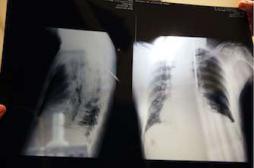

LES MALADIES

J'AI MAL